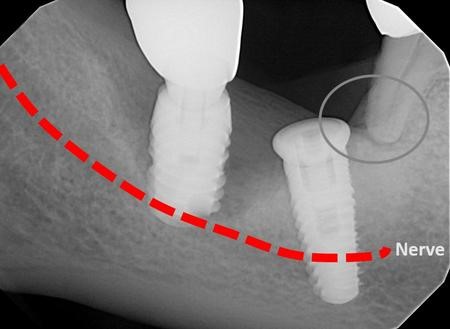

آسیب عصبی و اختلال حسی

یک دندانپزشک بی تجربه که خود آموز است و “کاشت ایمپلنت دندان انجام می دهد” ممکن است به طور تصادفی در طول عمل کاشت ایمپلنت دندان به اعصاب مجاور آسیب برساند. اعصاب فک مسئول ارائه اطلاعات حسی به دندان ها، لثه ها، لب ها و چانه هستند. در موارد کاشت نامناسب ایمپلنت دندان، اعصاب اطراف می توانند تحت تأثیر قرار گیرند و منجر به تغییر یا کاهش حس در این نواحی شوند. آسیب عصبی می تواند باعث مشکلات مختلفی مانند درد، سوزن سوزن شدن، بی حسی و حتی مشکل در صحبت کردن یا غذا خوردن صحیح شود. در موارد شدید، ممکن است برای ترمیم اعصاب آسیب دیده به مداخله جراحی نیاز باشد. برای جلوگیری از این نوع آسیب، همیشه به دنبال یک متخصص ایمپلنت دندان دارای مجوز و دارای بورد تخصصی باشید.